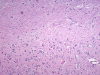

The excised specimen gave the features of cerebellum with greatly expanded cerebellar folia with myelination on the surface of the folia (Panel A, letter S indicates the material used to support the specimen) which can be seen easily on fresh specimen. . The expanded folia are most obvious in fixed specimen (Panel B). On pendicular section of the specimen (Panel C, arrow head points to the pial surface), the normal archicheture of cerebellum is totally effaced. The outer layer is composed of a layer of white matter while the inner half is composed of collections of large, ganglion cells ( in indicates the interface of the two layers which is magnified in Panel D). Multiple calcifications (darks spots in Panel C) are also present.The deeper layers of ganglion cells are composed of large, ganglioinic neurons of similar size and separated by only a small amount of glial tissue (Panel E and F). Multiple calcifications are seen in the more superficial layer of white matter (Panel G). Many calcified blood vessels (Panel H) are also noted in the deeper layers with ganglionic cells. The superficial white matter layer is well myelinated and strongly reactive for neurofilament (Panel I and J, stained by Luxol fast blue- Creysl Violet and immunohistochemistry for neurofilament respectively correspond to the interface indicated by the * in Panel C). The ganglionic cells are stronly reactive for neurofilament protien and synaptophysin (Panel K and L).

Histologically, a layer of myelinated fibers with large diameter myelinated axons is present in the more superficial location of the expanded where the molecular layer is found at the same level in normal cerebellum. The deeper layer where internal granule layer is supposed to be found is replaced by sheets intermediate sized to large dysplastic neurons that resemble Purkinje cells. In high magnification, these areas resemble gangliocytoma. The proportion of the myelinated outer layer and ganglionic inner layer is variable. The normal Purkinje cell layer is not found. Interspersed in between are much smaller neuronal cells with hyperchromatic, small nuclei that resemble hte internal granular layer. This is, therefore, essentially an “inside-out” architecture of the cerebellum with white matter on large ganglionic neuronal layer in the deeper layer. Mitotic figures are exceptional. Ki-67 labeling is 0-2% for the small number of cases that have been studied. The native white matter of the affected folia is atrophic and rarefied. The histologic features are very specific. Immunohistochemistry is not typically required for diagnosis.